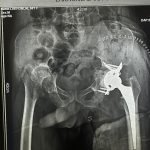

Orthopaedic Surgeon | Arthroscopy & Joint Replacement Specialist

Dr. Aditya Tripathi is a dedicated and skilled Orthopaedic Surgeon specializing in sports injuries, arthroscopy, and joint care. Known for his clinical precision, ethical practice, and patient-first approach, he focuses on helping patients regain mobility, strength, and confidence through evidence-based orthopaedic treatment. His academic background and hands-on clinical training reflect a strong foundation and a commitment to excellence in orthopaedic care.

Dr. Aditya Tripathi is widely appreciated by patients for his clear communication, honest medical guidance, and personalized treatment approach. His expertise in managing ACL tears, ligament injuries, shoulder conditions, and sports-related injuries makes him a trusted choice for comprehensive orthopaedic and sports injury care. Patients value his attention to detail, compassionate care, and focus on long-term recovery—establishing him as a reliable and respected orthopaedic specialist.

- Hip Replacement Surgery

- Fracture Treatment